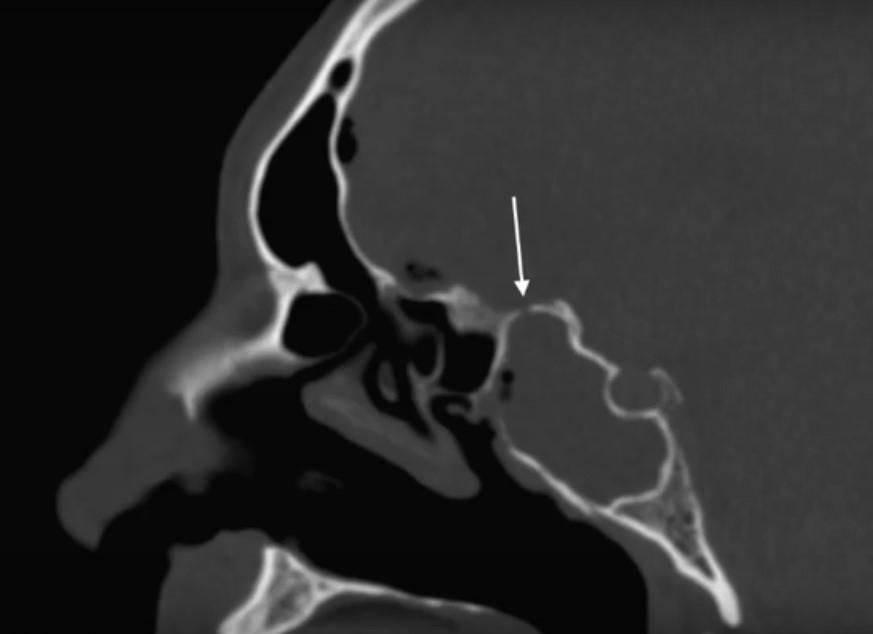

- КТ та МРТ для виявлення місця витоку.

- КТ (комп’ютерна томографія) з контрастом дозволяє виявити анатомічні дефекти та встановити точне місце витоку рідини.

- МРТ (магнітно-резонансна томографія) є додатковим методом для оцінки м’яких тканин та пошкоджень мозкових оболонок.

- КТ-цистернографія використовується для оцінки поширення контрастної речовини через свищевий канал.